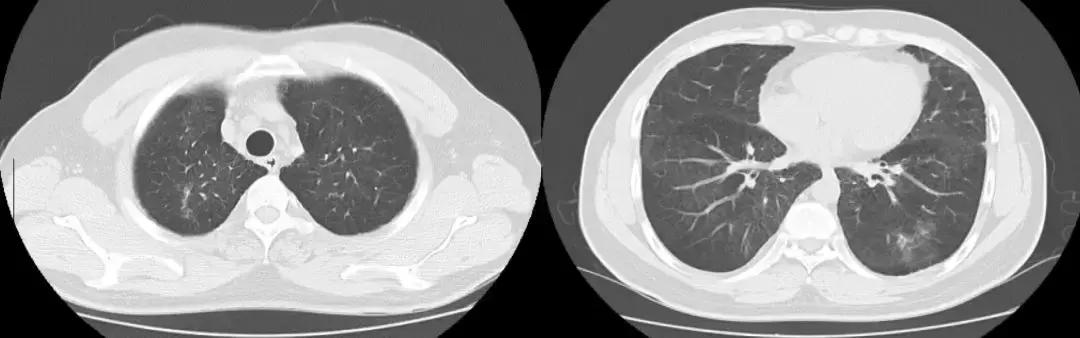

于北京协和医院查相关检查,如下图:

后给予强的松50mg 3月余。

复查胸部CT(2018-07-12):

左肺炎症较前好转,但肺部弥漫性病变较前变化不大。